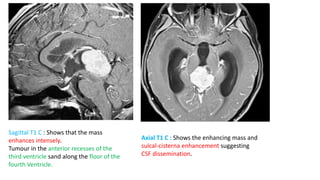

Sagittal T1 C : Shows that the mass

enhances intensely.

Tumour in the anterior recesses of the

third ventricle sand along the floor of the

fourth Ventricle.

Axial T1 C : Shows the enhancing mass and

sulcal-cisterna enhancement suggesting

CSF dissemination.